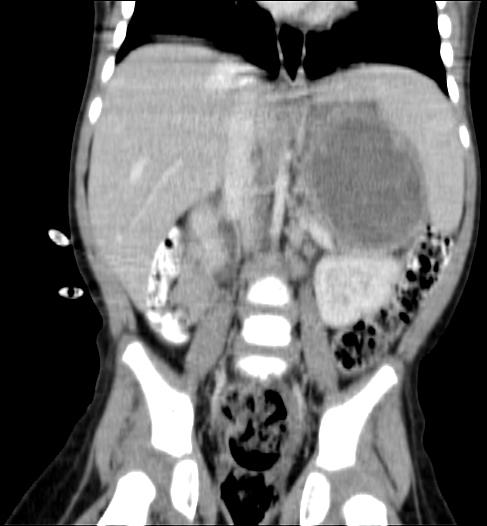

CT (CAT) scan 17July 2011